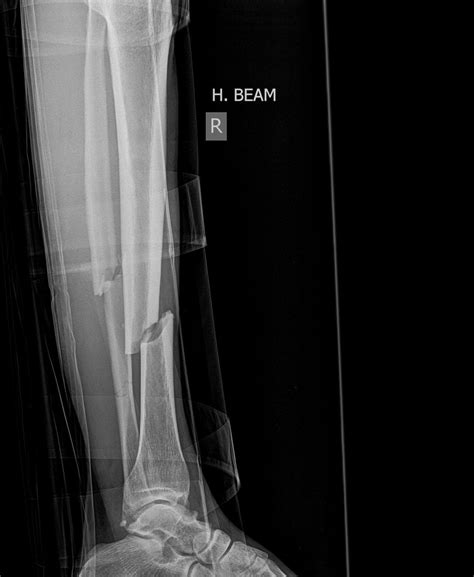

Signs Your Wrist Fracture Needs Surgery